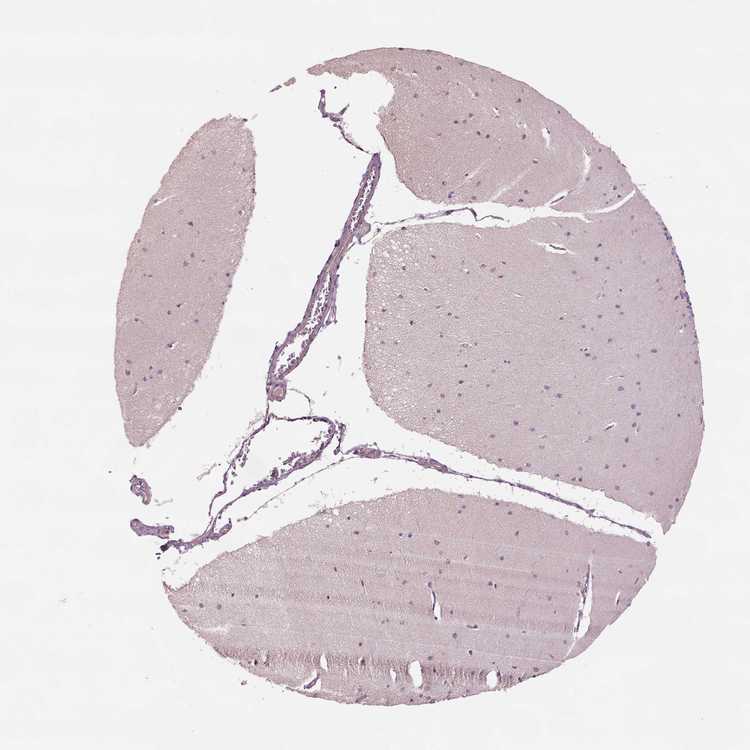

CEREBELLUM - Antibody stainingi

Antibody staining in the annotated cell types in the current human tissue is reported as not detected, low, medium, or high, based on conventional immunohistochemistry profiling in selected tissues. This score is based on the combination of the staining intensity and fraction of stained cells.

Each image is clickable and will lead to virtual microscopy that enables deeper exploration of all samples and also displays staining intensity scores, fraction scores and subcellular localization as well as patient and tissue information for each sample.

Antibody HPA069692

Purkinje cells Low

Cells in granular layer Low

Cells in molecular layer Low